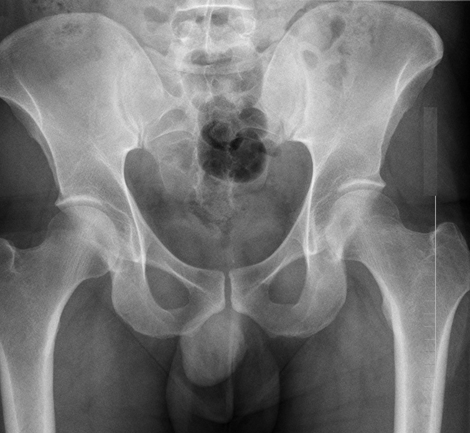

72岁的王奶奶,早晨下床不小心摔了个「屁股蹲」(摔倒,屁股坐地上)。老太太坐了会儿,自己就慢慢站了起来。尝试着走两步,虽然大胯那稍微有点疼,但并太影响走路。

王奶奶还去买了个菜,回家后还是觉得有点疼,但活动走路都不影响。王奶奶觉得可能是伤了筋了,就没往心里去。可家里孩子听了觉得不放心,上午就带老太太去了附近医院。急诊拍了大胯(髋关节)的片子,没有发现骨折。

可是,王奶奶歇了两天不但没好,反而疼痛越来越重了。尤其是伤的那边,脚一踩地就钻心的疼。家人不放心,再次带老太太去了医院,拍X光片依旧没看到有骨折。但是这次接诊医生很谨慎,给老太太查了髋关节的磁共振,结果发现:「股骨颈骨折」。

「有没有骨折,拍个X光片就知道了」,这是很多人觉得理所当然的事。然而,事实真的不是这样的,有些骨折X光片上真的看不出来。这不是某个医生水平不行,是真的看不出来。尤其是,有些大胯骨折(股骨颈骨折)。

国外一篇发表在2005年的研究中[1],医生们给急诊764例大胯外伤疼痛的患者拍了X光片,结果发现:有219人的X光片提示有骨折,有545人的X光片提示没有骨折。而后,医生给这525个X光片没有骨折的人都拍了磁共振(MRI),结果发现:

545个X光片没有骨折的患者中,有24个人被磁共振发现大胯有明确骨折。

同样的,在2005年发表的另外一篇国外研究[2]中,研究人员回顾了3年来的大胯受伤疼痛的患者,结果发现:

在100名X光片没看到骨折的患者中,后续的磁共振检查居然发现其中有46例有骨折。

所以,这也是为什么王奶奶尽管大胯都骨折了,但是拍了两次X光片都没有看到骨折。好在,最后医生给做了磁共振检查,发现了骨折,让王奶奶可以早期手术早期康复。